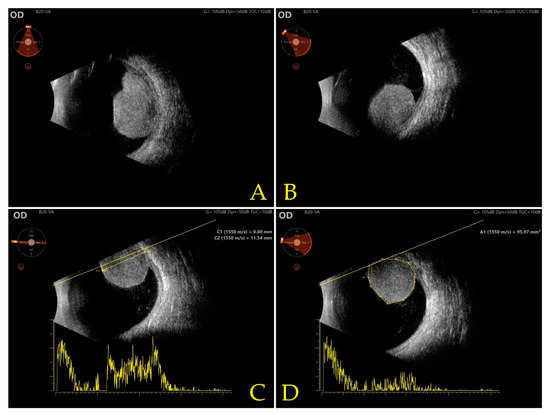

Case Presentation